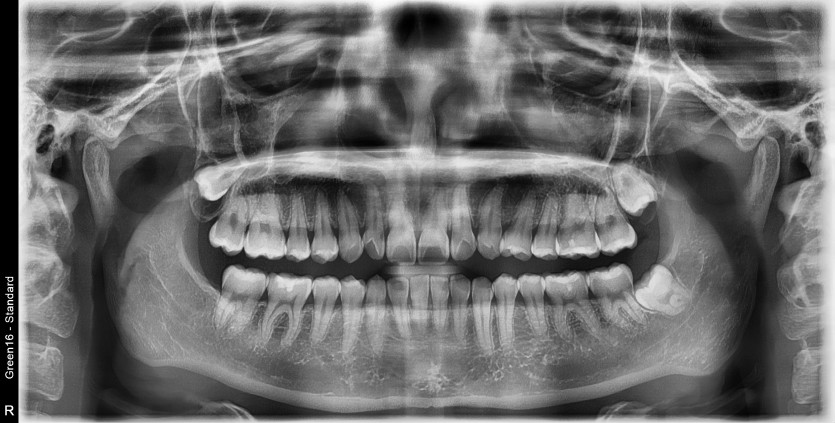

#28,38 사랑니 발치

구강 외과 전문의가 당일 발치했습니다.